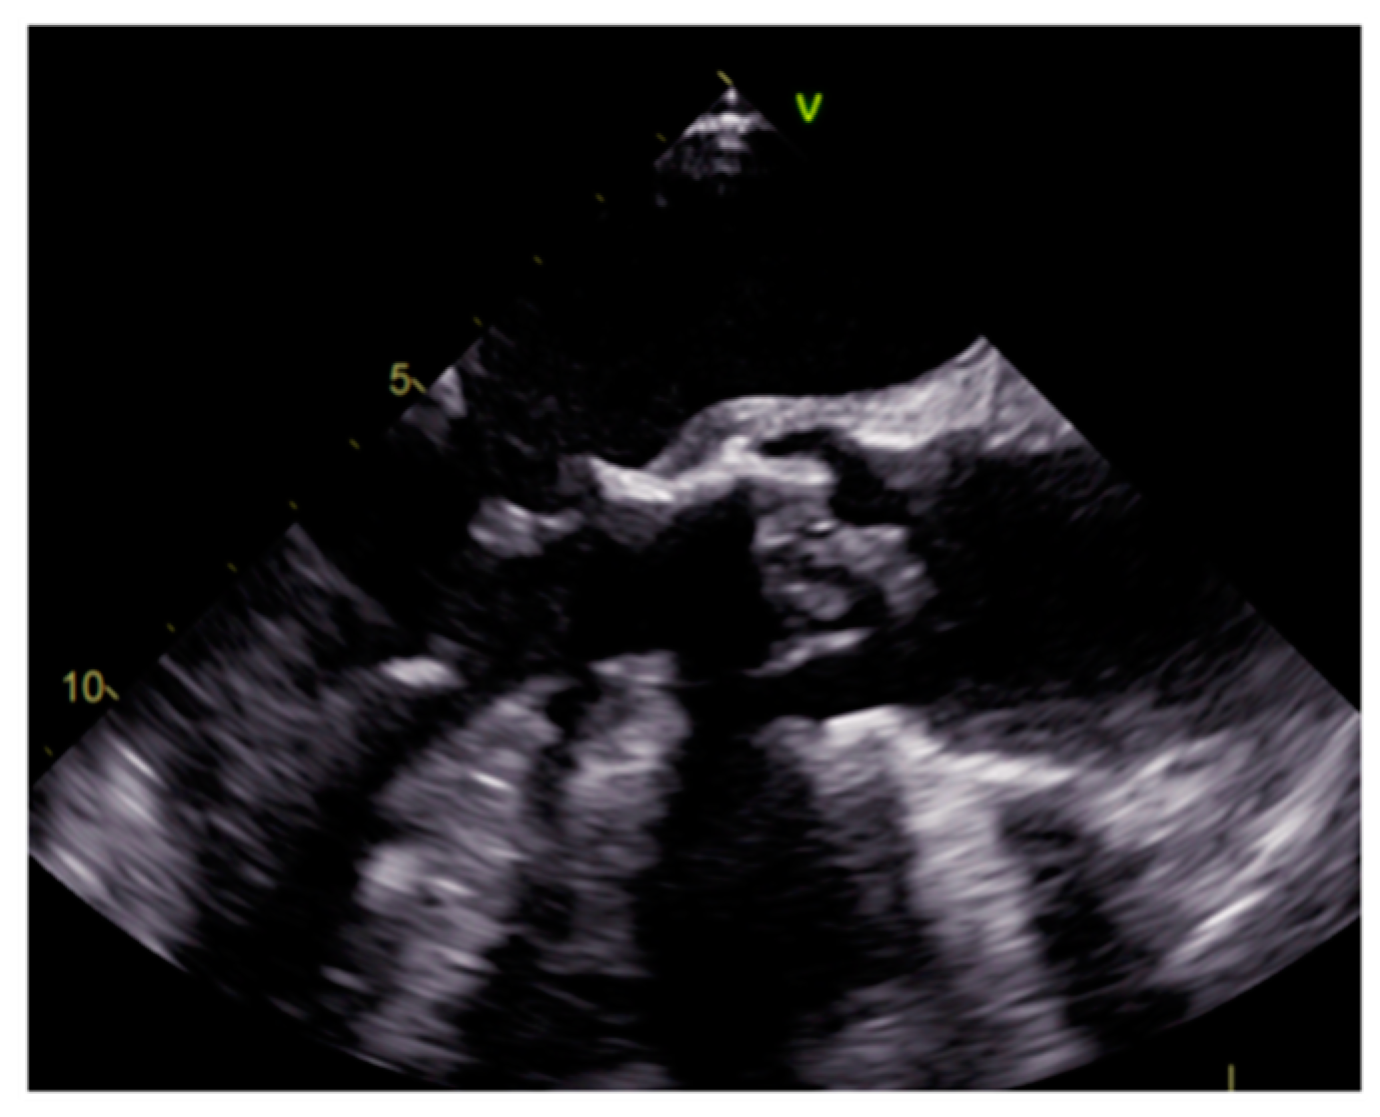

3.2. Vegetations

| Vegetations | Adulthood | Valves | Valve dysfunction, emboli, heart failure | Highly mobile, non-enhancing | Highly mobile, oscillating, protruding, valve dysfunction | Low attenuation, may recognize, perivalvular extension, fistulas, abscess | Highly mobile |